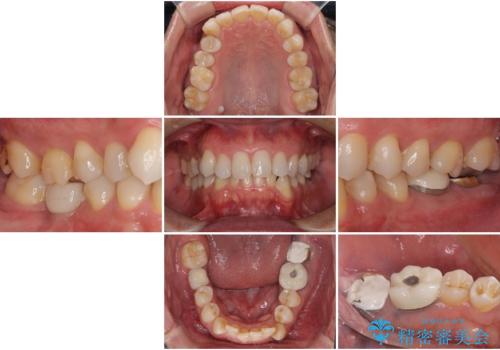

- 近医にて奥歯の抜歯が必要と言われたとのことで来院された患者様です。

診査の結果、歯が破折しており、抜歯が必要な状態でした。

最後方歯であるため、入れ歯かインプラントかどちらかの補綴治療を行うこととなりますが、ご希望によりインプラント補綴治療を行うこととしました。

インプラントにはストローマン社のSLActiveを使用し、埋入から補綴までおよそ3か月と、短期間で治療を進めることができました。